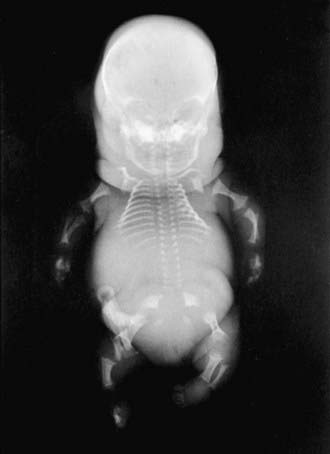

Achondrogenesis type II (OMIM 200610) is characterized by severe shortening of the neck and trunk and especially the limbs and by a large, soft head. Fetal hydrops and prematurity are common; infants are stillborn or die shortly after birth. Hypochondrogenesis (OMIM 200610) refers to a clinical phenotype intermediate between achondrogenesis type II and SED congenita. It is typically lethal in the newborn period.

The severity of radiographic changes correlates with the clinical severity (Fig. 686-1). Both conditions produce short, broad tubular bones with cupped metaphyses. The pelvic bones are hypoplastic, and the cranial bones are not well mineralized. The vertebral bodies are poorly ossified in the entire spine in achondrogenesis type II and in the cervical and sacral spine in hypochondrogenesis. The pedicles are ossified in both.

Figure 686-1 Stillborn infant with achondrogenesis type II. Note poor ossification of calvaria, vertebral bodies, and sacrum; hypoplasia of pelvic bones; and short tubular bones with cupped metaphyses.